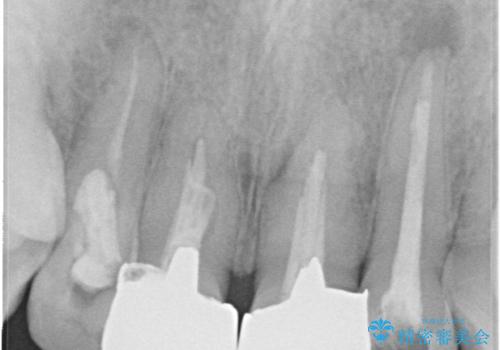

- 上の前歯の見た目が気になるとのことで来院されました。

上の前歯の4本が神経の処置がされており、前から2番目の歯が内側に入り込んでしまっていました。

また、金属で治療された根本の歯茎が黒く変色(メタルタトゥー)しており、余計に見た目がよくない状態となっておりました。